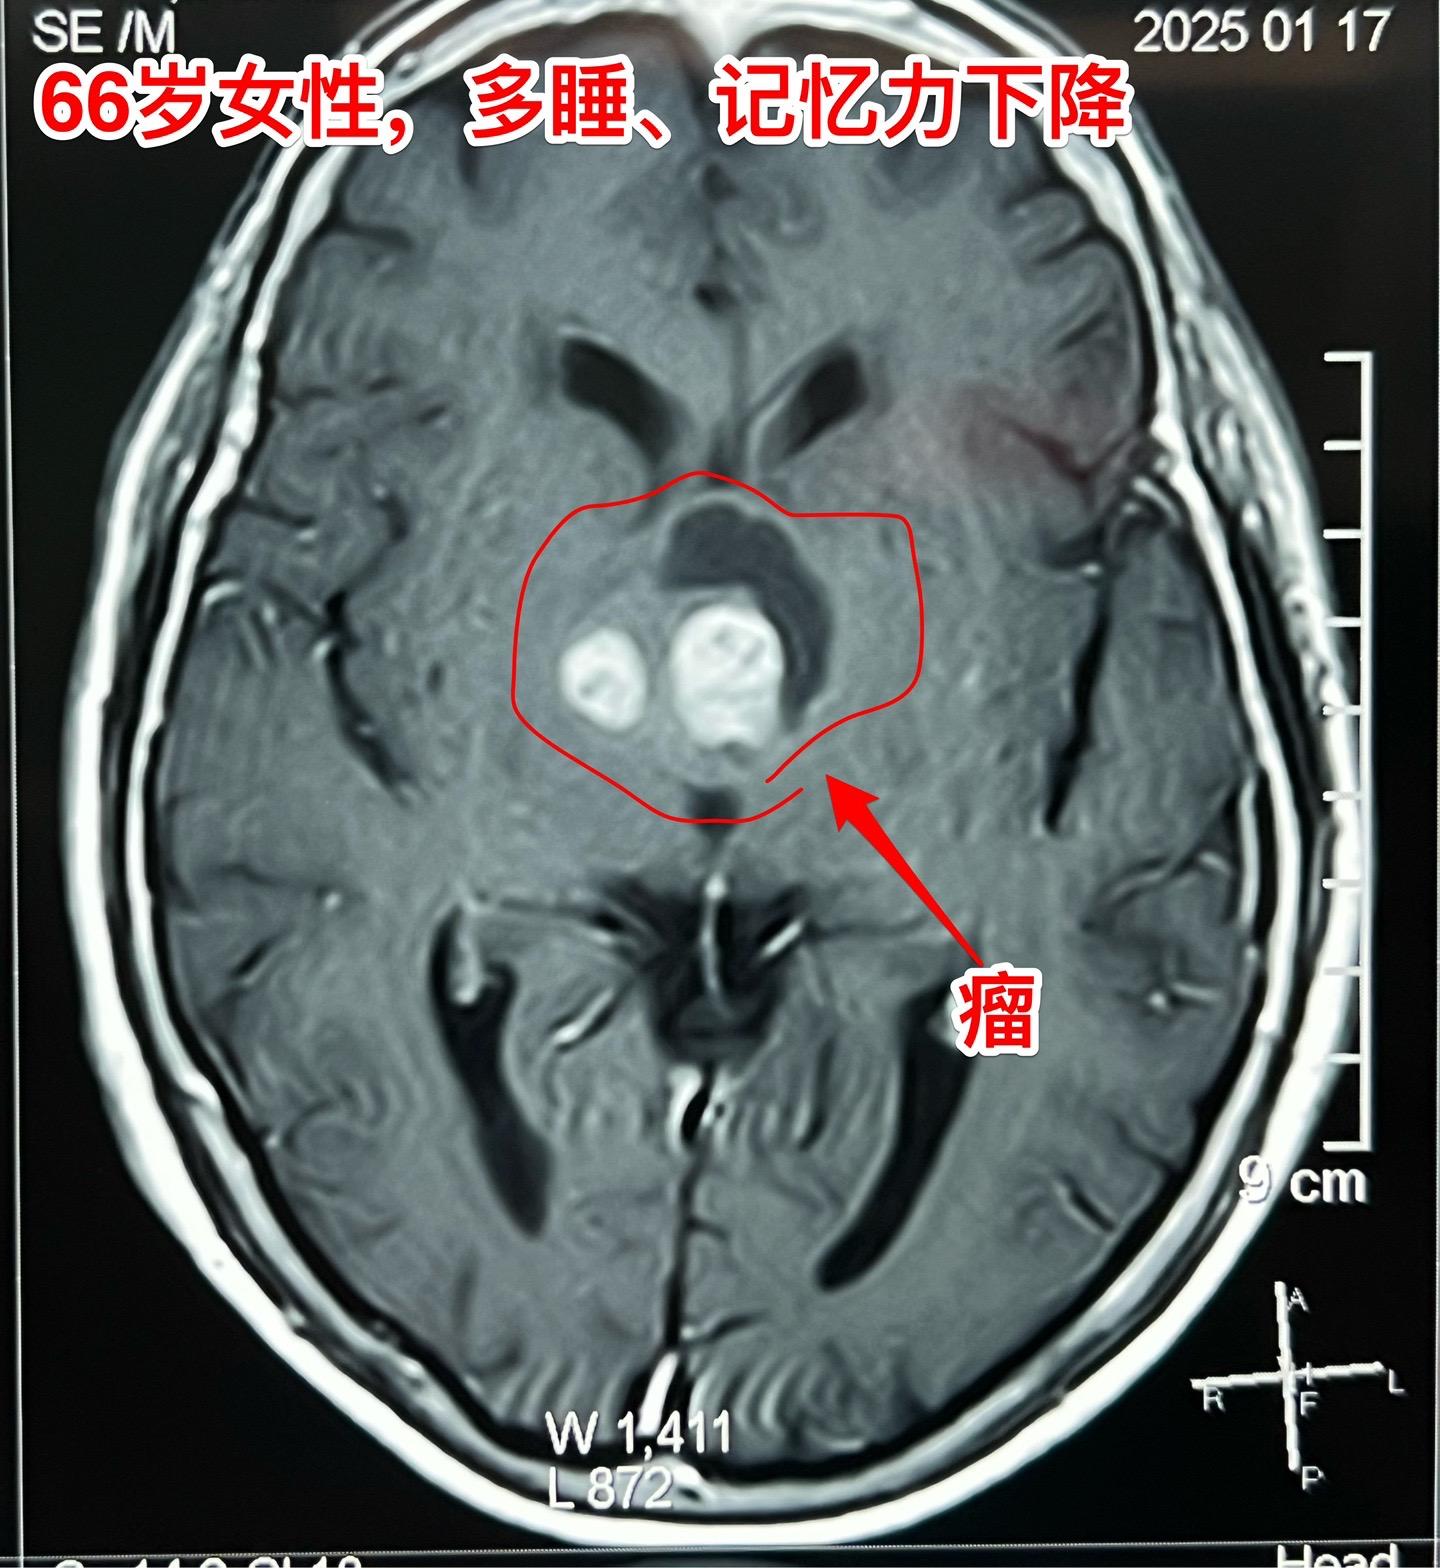

是颅咽管瘤吗?鞍区肿瘤的定性诊断是很难的。66岁女性,泰州人。因为多睡、记忆力下降在外院检查脑部发现脑部肿瘤。病人的多睡症状越来越严重。肿瘤位于鞍上区域,而且伴有脑积水。外院怀疑是颅咽管瘤?或者是别的肿瘤? 病人曾经在上海就医过,因担心手术风险,通过三博脑科医院院长找我咨询,随后决定到我院作手术。 1月24日作了开颅手术(这是我科春节前的最后一个择期手术),手术中发现肿瘤的性状不符合乳头型颅咽管瘤,分两次取标本送快速冰冻病理检查,报告考虑是胶质瘤。 下丘脑胶质